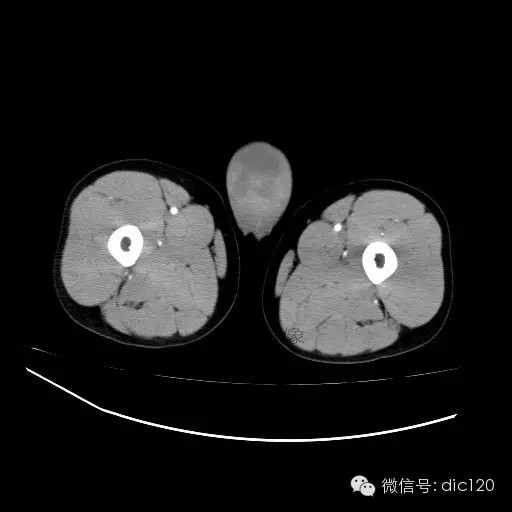

青年男性,右侧睾丸肿大,边界清晰,增强后睾丸不均匀中度强化,内可见多灶囊变坏死区,动脉期肿块内有细小动脉血管显示,延迟期可见分隔样强化,鞘膜囊可见积液。

定位定性:右侧睾丸恶性肿瘤。

【影像诊断】

右侧睾丸精原细胞瘤,右侧睾丸鞘膜积液。